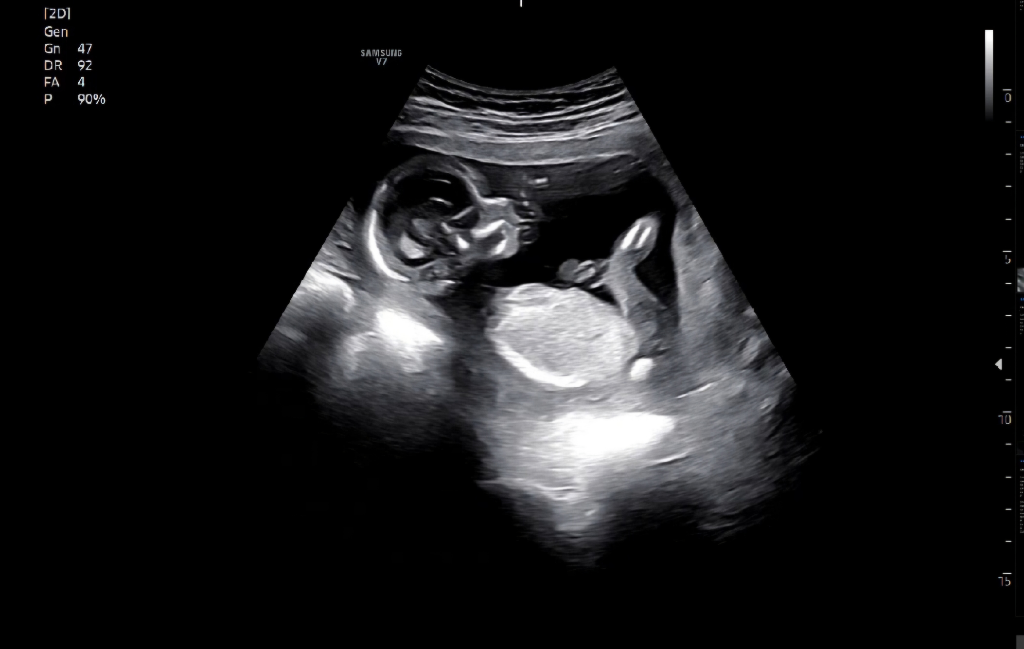

이는단순수치적수치랍니다

그렇기에아직걱정할건아니며

이후양수검사까지는다운증후군으로볼순없답니다